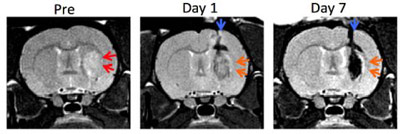

At the hospital, nerve function tests can help provide clues as to which parts of the brain are affected by the stroke and how severe the damage is. Blood collection and testing provide information on, among other things, blood counts, blood clotting, inflammatory parameters, and risk factors such as elevated cholesterol or blood glucose levels. The medical team can then use imaging techniques such as CT Scan (computed tomography ) or MRI scan (magnetic resonance tomography) to scrutinize the patient’s brain. The radiology scans are especially helpful to diagnose if the patient has an ischemic or hemorrhagic stroke is present, detect circulatory disorders or existing cerebral hemorrhages. In addition, the cerebral vessels can be also be visualized by a CT angiography to detect blockages.

Neural stem cell therapy uses the paracrine cell signaling method to target the damaged part of the brain’s neural circuitry that controls motor functions. The cells are first enhanced in our stem cell lab then injected intravenously, via a proprietary stem cell nebulizer treatment to deliver cells near the motor neuron tracts close to the lesions in an attempt to promote regeneration and repair through the section of Cytokines and nerve growth factors. The benefits are gradual; however, most patients show immediate improvements after the first or second infusions and continue to show improvement 3-6 months post-therapy. The results are permanent but will require consistent physical and speech rehabilitation after treatment to allow the brain to return to proper function, especially for cases with cerebral hemorrhaging and cerebral infarction.[3]

before-after-stemcells-stroke-brain